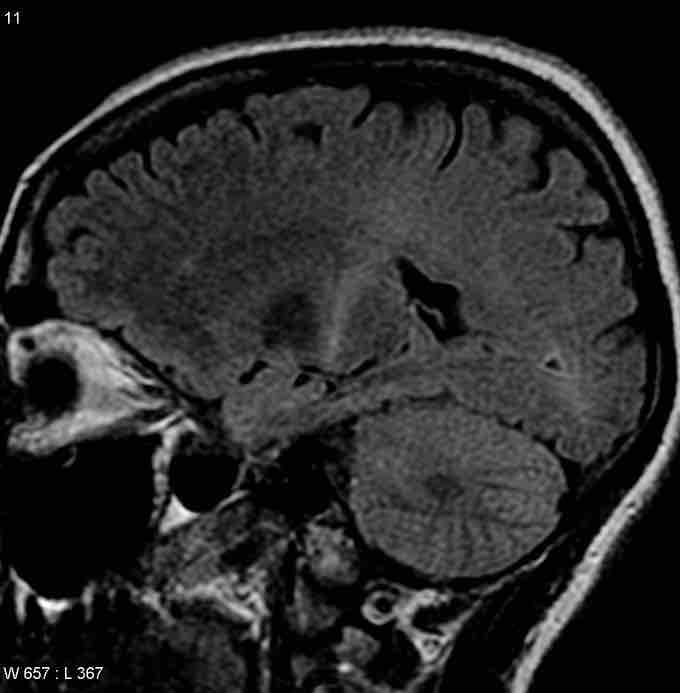

Coronal MRI of an ALS patient

MRI (parasagittal FLAIR) demonstrates increased T2 signal within the posterior part of the internal capsule and can be tracked to the subcortical white matter of the motor cortex, outlining the corticospinal tract), consistent with the clinical diagnosis of ALS.